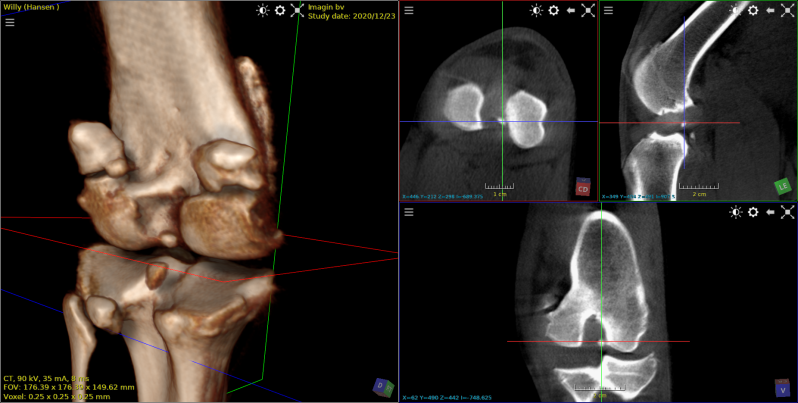

lossse processus coronoideus teckel

losse processus coronoideus  spaniel 4 maanden oud